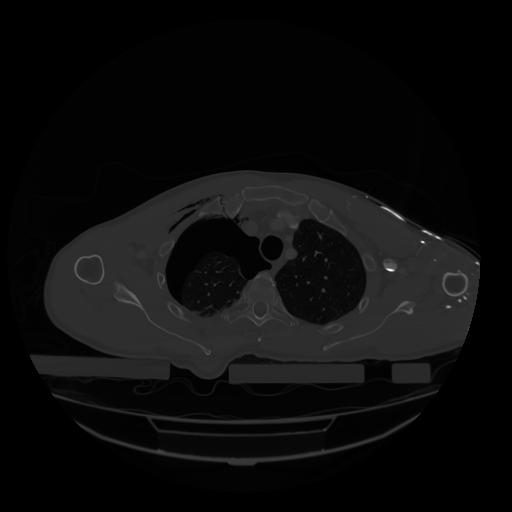

28 CUERPO,CE,Vol,2.0,CUERPO,,